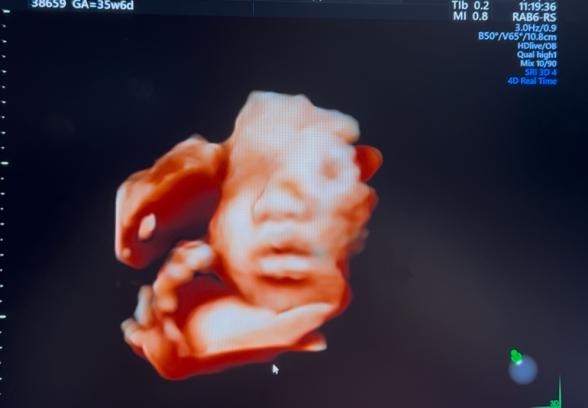

妊婦健診で4Dのエコー写真を撮って頂けるのですが、

顔の特徴がダウン症の特徴と同じのような感じがして

不安です。鼻は低いし目がつり目?のような浮腫んでるような…。

※写真は28週、35週、32週の順です。

実際にエコー写真でダウン症顔貌かの判断は、できないかなと思います。私からみて、エコーでみる赤ちゃんの顔としては、特徴的な顔貌の印象はないです。

エコー画像は、実際に見る感じとは、少し違う感じに見えるかなと思います。